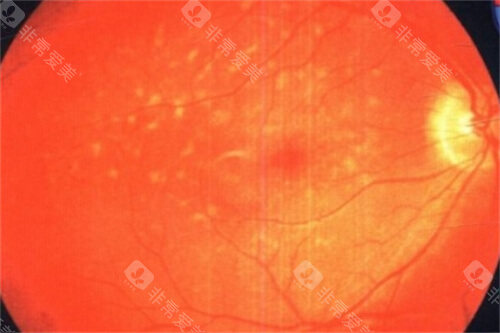

术前,患者需接受超全眼科检查,包括视力测试、眼底检查和OCT扫描,以评估病情并制定手术方案。

首可靠行玻璃体切除,清除眼内玻璃体以提供清晰视野;随后使用特定染色剂(如亮蓝)使黄斑前膜显色,便于比较准操作。

在显微镜下,医生用精细工具(如视网膜钩或镊子)小心抓住并剥离前膜,尽量减少对视网膜的损伤。

剥除后,详细检查视网膜表面是否有残留膜,并清理干净。然后,向眼内注入平衡盐溶液维持眼球形状,闭合切口。